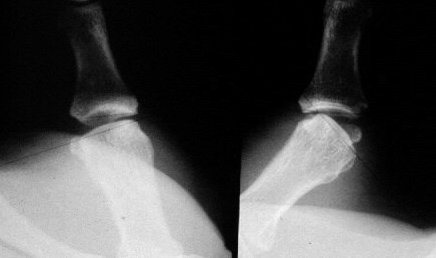

Questionable cases can be evaluated with stress Xrays to determine just how far off track the joint deviates:

Films are compared with and without stress. This thumb not only translates radially, but "opens up", indicating a complete ligament tear.

This thumb translates about 40% to the side, but does not open up: still a complete disruption.